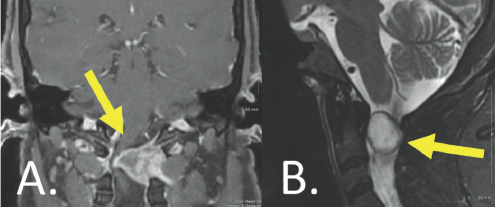

The surgery was performed with Isabella in the prone position. Blood pressure was carefully managed by the anesthesia team and neuro-monitoring was used to optimize safety. Following exposure and boney removal, Dr. Forbes meticulously dissected the tumor free from the spinal cord under magnification and removed it without complication. A tissue sample was sent to pathology, which confirmed the tumor was a benign neurofibroma. Isabella did extremely well following the surgery. Shortly after the procedure, she began to notice the strength in her extremities was improving. At her one-year follow-up visit with Dr. Forbes, she had regained a great deal of strength and was now able to ambulate without using a cane. Repeat MR imaging did not show any evidence of residual or recurrent tumor tissue (Figure 4.2); other images showed that her spinal column remained perfectly stable. At this visit, Isabella happily reported that she was now able to enjoy hikes and other outdoor activities with her young daughter for the first time in many years.

(Left) Gray and white color variations are surrounded by a gray outline. There is a gray colored column attaching a large gray space to the bottom of the image. (Right) A light grey vertical column is shown surrounded by white coloration from the bottom to the top of the image. There are other gray structures present, all of which are enclosed by a dark gray outline.

FIGURE 4.2 Coronal, T1-weighted, post-contrast (A) and sagittal, T2-weighted (B) imaging demonstrates no evidence of residual or recurrent tumor one year following resection. All mass effect has been relieved, and the spinal cord has re-expanded.